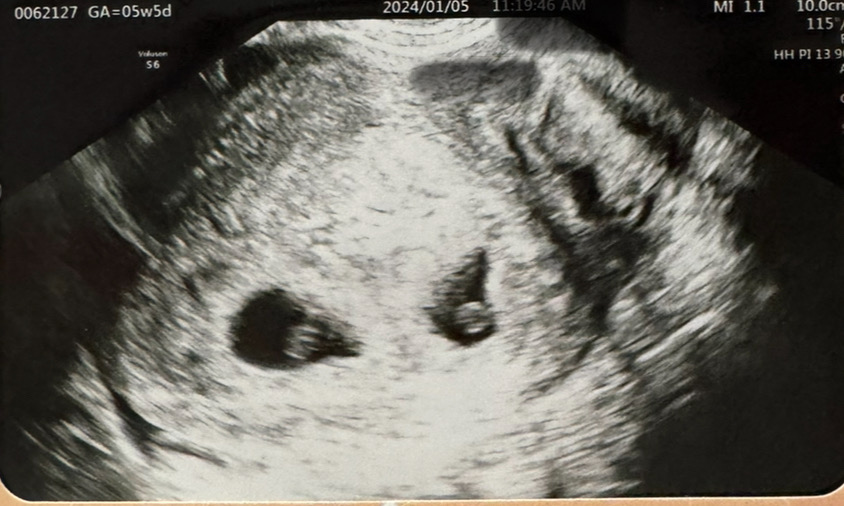

저도 이번에 자연임신 둥이에요! 5주부터 입덧 있다고 하니까 의사선생님께서 쌍둥이면 입덧도 더 심할텐데...라고 하셨어요ㅠㅠ

쌍둥이는 입덧도 두배로 심한가요..ㅠㅠ

계획임신 한방에 유전에도 없는 둥이가 찾아와서 아직도 얼떨떨하고 신기한 하루하루를 보내고 있어요ㅎㅎ 6주차 부터 입덧증상이 시작 되더니, 빈속에는 배멀미처럼 속이 너무 미식거리고 먹어도 살기위해 먹는수준일 만큼 꾸역 꾸역 먹고 있어요.. 먹은 후에도 속이 그리 편하진 않아 일주일째 무기력하게 누워만 있다가 입덧약도 처방받아 먹었는데 2알까진 아무 효과가 없어요ㅜ 3알.. 4알...까지 먹어야 하는건지 둥이라 심한건지 궁금해요ㅠㅠ